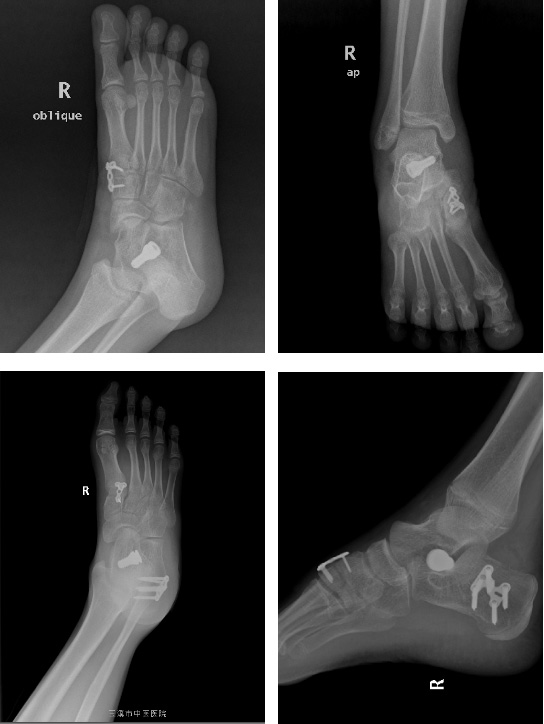

5. 經(jīng)過上述保守治療,若患兒癥狀改善不明顯,可行手術(shù)治療,以矯正平足從而緩解癥狀。